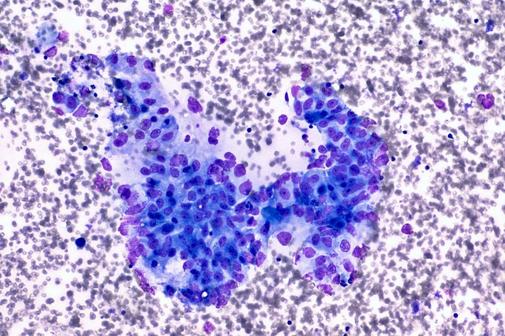

Ensayo lanza resultados prometedores contra el cáncer de páncreas metastásico

El estudio busca evaluar la seguridad y la actividad antitumoral de mitazalimab, un anticuerpo IgG1 agonista de CD40 humano.

El estudio busca evaluar la seguridad y la actividad antitumoral de mitazalimab, un anticuerpo IgG1 agonista de CD40 humano. -

Prueban tratamiento que frena mutación del cáncer de páncreas

Se trata del primer ensayo clínico en humanos de un tratamiento que modifica los inhibidores del oncogén KRAS, las regiones del ADN relacionadas con este cáncer.

Se trata del primer ensayo clínico en humanos de un tratamiento que modifica los inhibidores del oncogén KRAS, las regiones del ADN relacionadas con este cáncer. -

Descubren medicamento que frena propagación de cáncer de páncreas

El medicamento olaparib redujo el riesgo de progresión de la enfermedad en un grupo de pacientes que participaban en un examen médico.

El medicamento olaparib redujo el riesgo de progresión de la enfermedad en un grupo de pacientes que participaban en un examen médico. -

Científicos del CNIO logran eliminar cáncer de páncreas en ratones

El doctor Mariano Barbacid, quien lidera el equipo, dijo que se trata de un primer paso y que se debe seguir investigando.

El doctor Mariano Barbacid, quien lidera el equipo, dijo que se trata de un primer paso y que se debe seguir investigando.